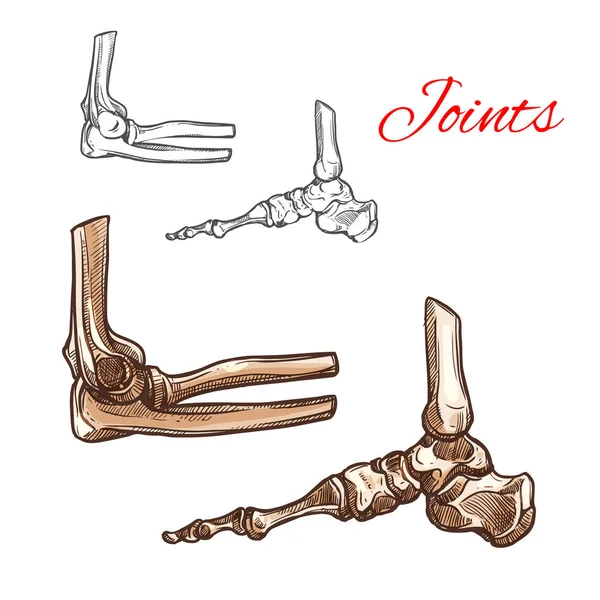

กระดูกเท้าร่างกายวิภาคของมนุษย์ ภาพประกอบสต็อก – ดาวน์โหลดรูปภาพตอนนี้ …

กระดูกเท้าร่างกายวิภาคของมนุษย์ ภาพประกอบสต็อก – ดาวน์โหลดรูปภาพตอนนี้ … เท้าผิดรูป เกิดจากอะไร ต้องรักษาอย่างไร มีแบบไหนบ้าง มาดูกันครับ

Bones Foot Ankle Joint Medical Vector: immagine vettoriale stock … โครงกระดูกไดโนเสาร์, ภาพตัดปะฟอสซิล, ศิลปะฟอสซิลคลิป, ฟอสซิลภาพ PNG และ …